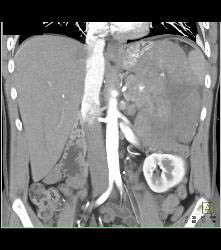

GIST Tumor With Ulceration